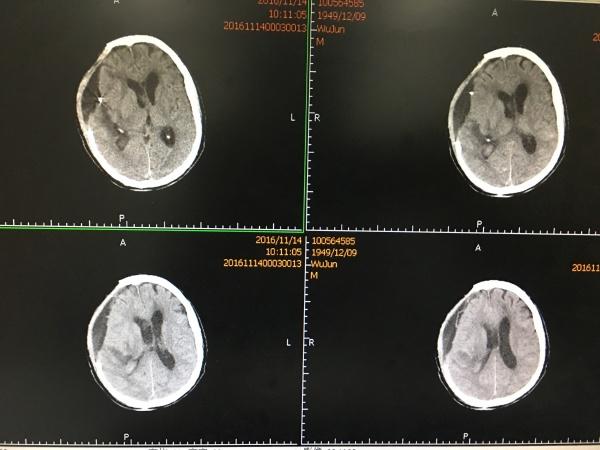

见MCA供血区大面积梗塞,查凝血无明显异常,予以改善微循环、扩容等对症治疗,1周后再次复查CT:

CT所见MCA供血区梗塞明显好转,骨窗处见硬膜下积液,此时患者评分改善,刺痛可睁眼,有摸索动作。

再过一周,再次复查CT示:

硬膜下积液较前稍增加,中线基本回位,积液未造成明显占位效应,故我们决定继续观察,必要时可以予以Ommayya囊植入、积液引流术。